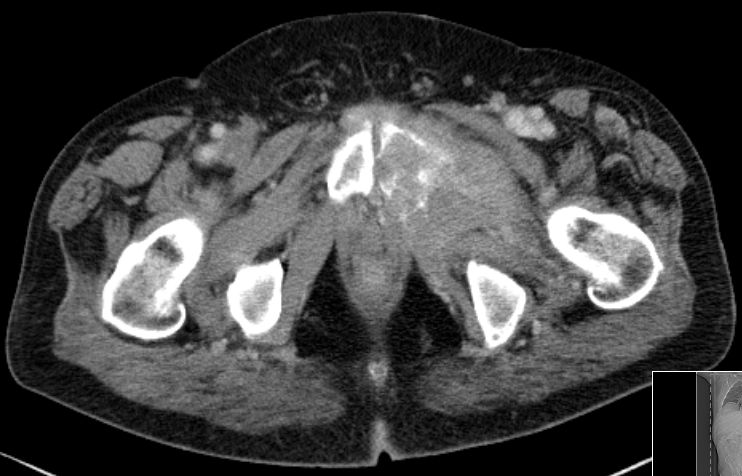

| Knochenmetastasen | 61-jähriger Patient, der vor 2,5 Jahren ein primär hepatisch metastasiertes Rektumkarzinom hatte.

9 Monate FOLFIRI/Erbitux ergaben eine CR der Lebermetastasen.

Mit verschiedenen systemischen und chirurgischen Maßnahmen Tumorkontrolle bis jetzt.

Nun Schmerzen in der linken Leiste besonders beim Treppensteigen.

Das CT zeigt eine Schambeinmetastase mit großem Weichteiltumor.![]() |

Der Weichteiltumor ragt nach caudal in den Adduktorenkanal.![]() |

Cranial ist das symphysennahe Schambein völlig zerstört.![]() |